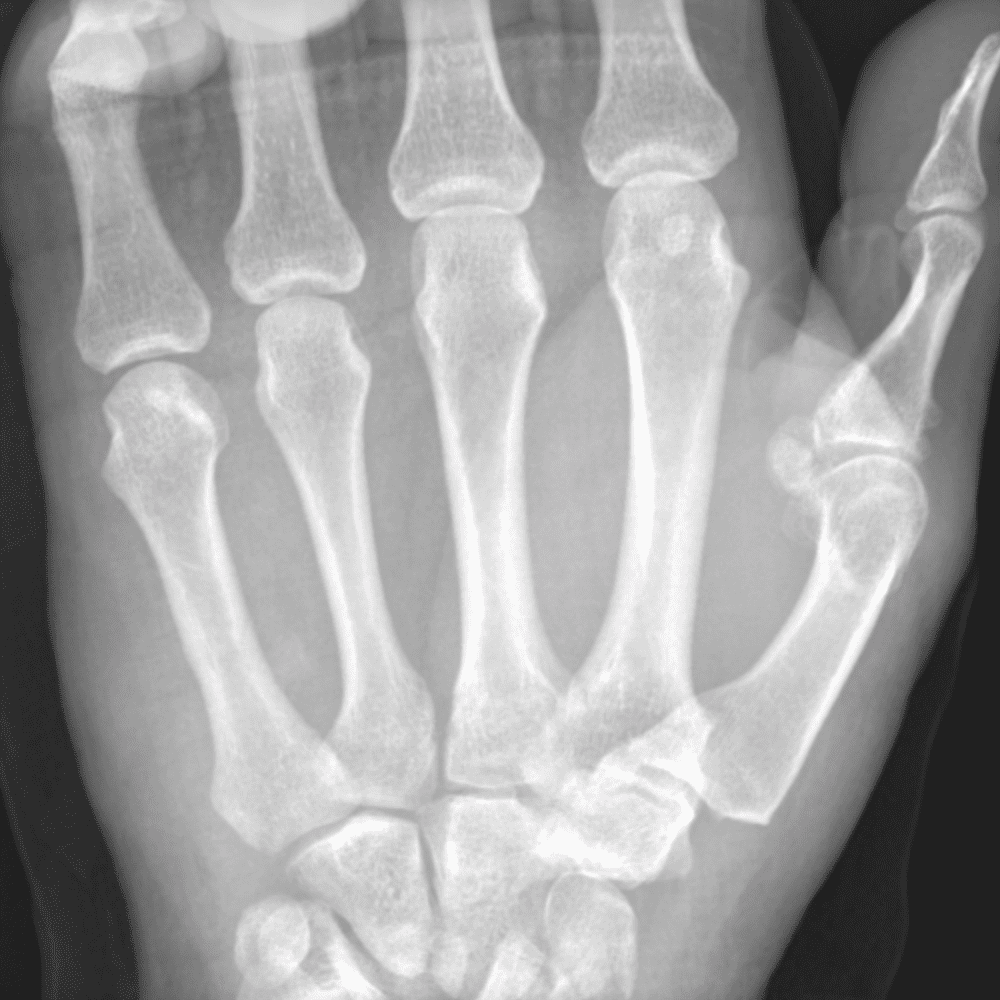

Simuliert den Dienst durch subtile oder schwierige Fälle und einige Normalbefunde.

30 Fälle